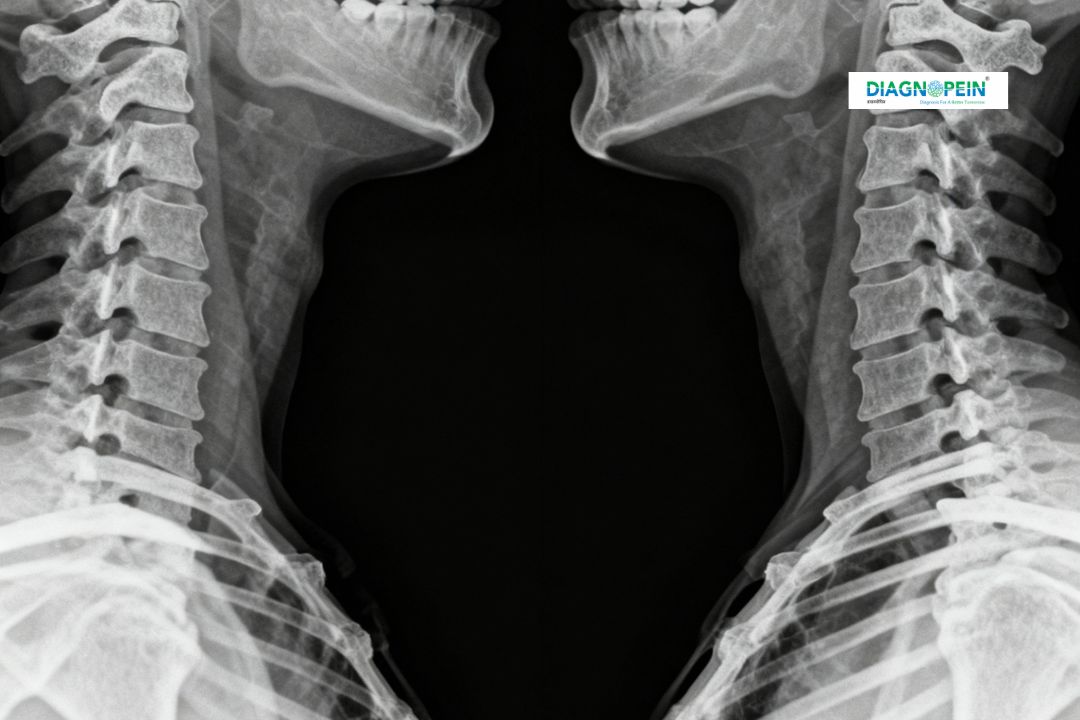

The cervico-thoracic spine connects the neck and upper back, supporting head and shoulder movement while protecting the spinal cord. The X-Ray Cervico-Thoracic Spine AP (Anteroposterior) and Lateral views capture front-to-back and side perspectives of this crucial junction, revealing structural changes, injuries, or abnormalities.

In karad, Diagnopein’s digital X-ray systems offer quick, high-resolution images that assist doctors in diagnosing fractures, dislocations, osteoarthritis, disc degeneration, and post-surgical assessments.

1. Alignment of vertebral bodies from C1 to T3

2. Bone density and joint space between vertebrae

3. Presence of bone spurs or structural deformities

4. Curvature of the spine (lordosis or kyphosis)

5. Soft tissue shadows and spinal canal width

These imaging parameters help detect abnormalities and guide orthopedic or neurological management effectively.